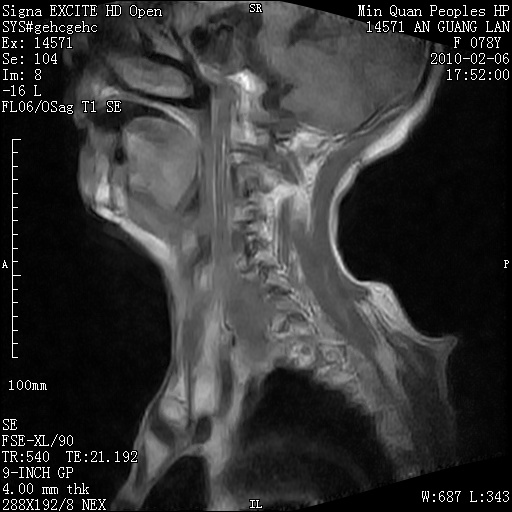

标题: MRI2763:C6、C7椎体病变性质?

f,78y,颈部与双上肢阵发性剧痛40余天。ct可见c6、c7椎体虫蚀样破坏,其间椎间隙变窄(没有图片资料可供上传)。